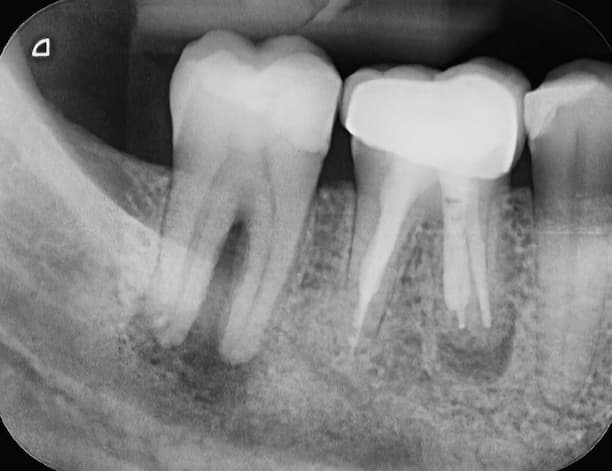

A fogászati góc kialakulását röntgenfelvételek, esetleg CBCT segítségével lehet diagnosztizálni. Gyógyítani a góc eltávolításával lehet. Ennek egyértelmű módja a fog eltávolítása. Mivel minden gyanús fogat nem lehet eltávolítani, ezért megpróbálkozunk – pl. fogtöméssel, gyökérkezeléssel, gyökércsúcs amputációval, a fogágy betegség komplex kezelésével – az elsődleges gyulladás megszüntetésével.